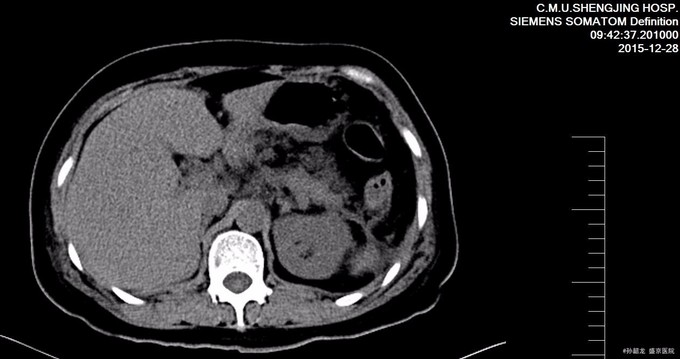

查体: 双侧乳腺缺如。腹平坦,未见胃肠型及蠕动波,腹壁无静脉曲张,左腹部可见经腹直肌切口瘢痕约20cm,以及两点状瘢痕。肝脾肋下未触及,未触及包块,全腹轻压痛,反跳痛,腹直肌紧张。Murphy’s征阴性,肝肾区无叩痛,移动性浊音阴性,肠鸣音4次/分。 辅查: 胰腺CT提示胰腺稍肿胀,轮廓模糊,胰周见模糊渗出及积液,胰腺前方腹腔内渗出。左侧肾前筋膜及邻近腹膜增厚,左侧结肠旁沟内见积液。 肝脏密度仍减低;胆囊内胆汁密度增高。扫描范围左侧胸腔积液。 腹部BUS 提示腹腔积液。 血淀粉酶和脂肪酶明显升高,血甘油三酯和胆固醇升高。